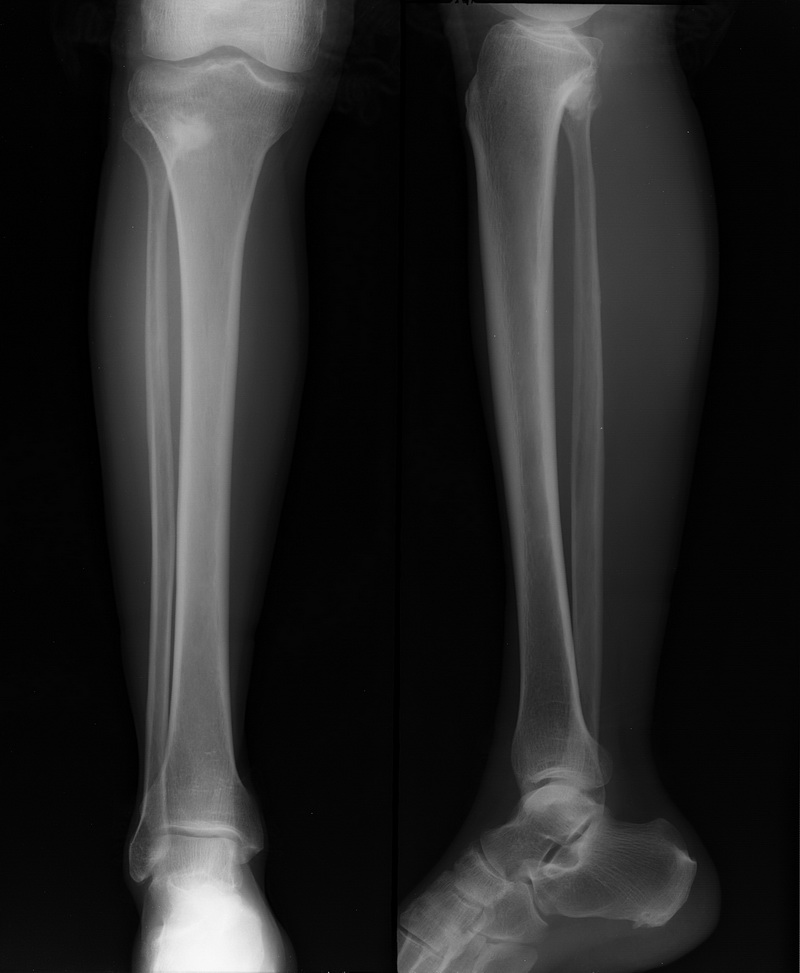

男 62岁  外伤来院

照个斜位看看,考虑-----腓骨骨软骨瘤可能。

腓骨骨软骨瘤可能

骨软骨瘤

考虑:骨梗死

胫骨外侧髁应当有骨折。

腓骨小头骨软骨瘤。

胫骨外侧髁骨折,骨软骨瘤。

腓骨上端骨软骨瘤可能。胫骨外上髁似有骨折

腓骨骨软骨瘤,胫骨外侧髁骨折可疑。

形态位置上支持骨软骨瘤,不知密度为何如此高